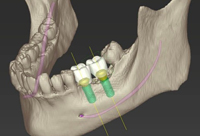

ショートインプラントを用いたシミュレーション

ショートインプラントは、骨移植や骨造成を行わずに治療ができ、身体的負担の軽減、治療期間の短縮、そして経済的な治療法です。

- 3Dコンピューターシミュレーションにて設計